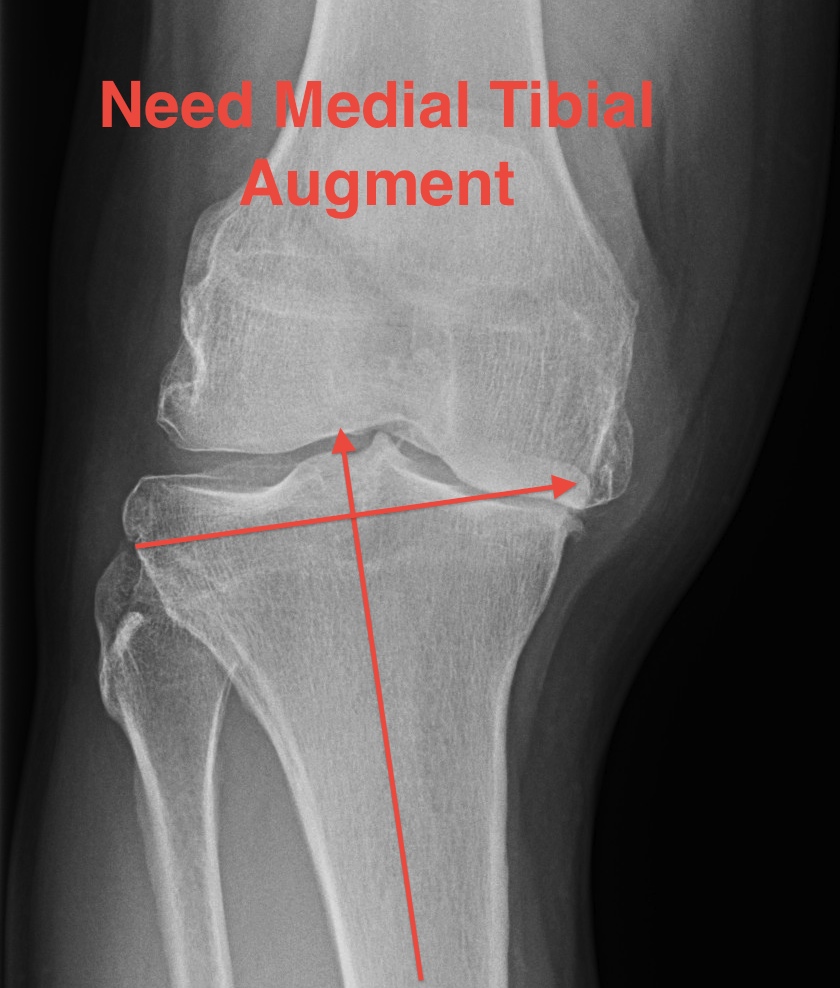

Severe varus deformity

Problem

- 10 mm from lateral side does not take medial bone

- do not cut to level of medial defect as cancellous bone of the tibia becomes weak

Solution

- stay subchondral on lateral side

- never more than 10 mm cut lateral side

- build up medial side

Options

1. Cement

2. Autologous bone graft

- may have enough in primary

- from posterior or distal femoral condyles

- supplement with 2 screws

3. Augments

- 5 - 10 mm

- use stems if use augments

- offsets forces to the diaphysis (up to 30%)